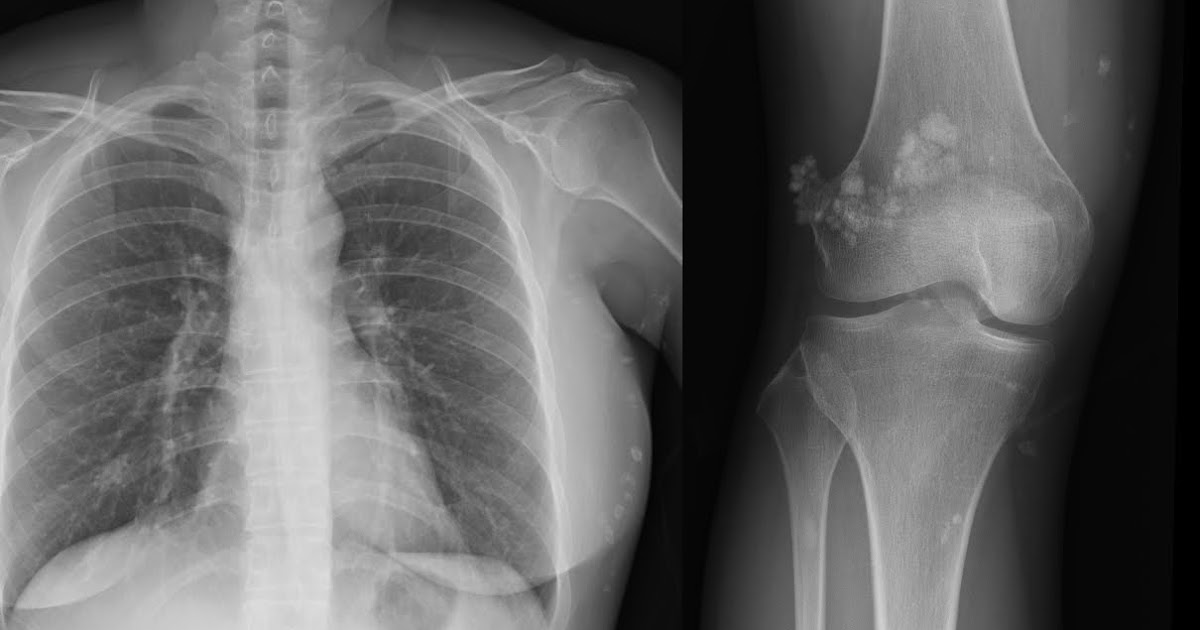

Chest XRay Calcium Sign Aortic dissection, Aortic aneurysm

Chest XRay Calcium Sign Aortic dissection, Aortic aneurysm Calcium Deposits On X Ray    calcium pyrophosphate dihydrate deposition (cppd) disease, also known as pyrophosphate arthropathy or pseudogout, is defined.   hydroxyapatite crystal deposition disease (hadd) or calcium apatite deposition disease (cadd) is a disease of uncertain.   abdominal calcifications are common and have many causes.   doctors classify nephrocalcinosis as molecular, microscopic, or macroscopic. The classification depends on the size of the calcium.. Calcium Deposits On X Ray.

Aortic Calcification On Chest X Ray Calcium Deposits On X Ray    doctors classify nephrocalcinosis as molecular, microscopic, or macroscopic.   medial artery calcification (mac) is a condition characterized by the presence of diffuse calcium deposits.   hydroxyapatite crystal deposition disease (hadd) or calcium apatite deposition disease (cadd) is a disease of uncertain. The classification depends on the size of the calcium.   abdominal calcifications are common and have many causes.. Calcium Deposits On X Ray.